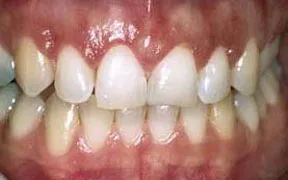

This patient was unhappy with her gummy smile. The gum tissues covered up too much of the teeth, making the teeth look too short.

A crown lengthening procedure was performed, which evened the height of the gum tissue across the front teeth. The result was dramatic and the patient was quite pleased.